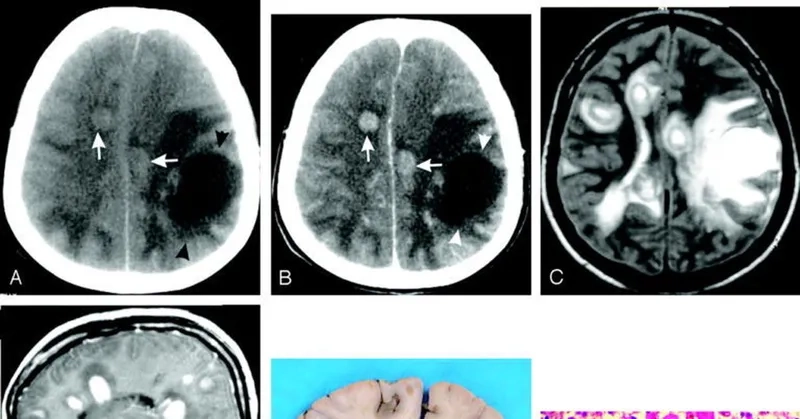

Image of the disease Primary Amebic Meningoencephalitis